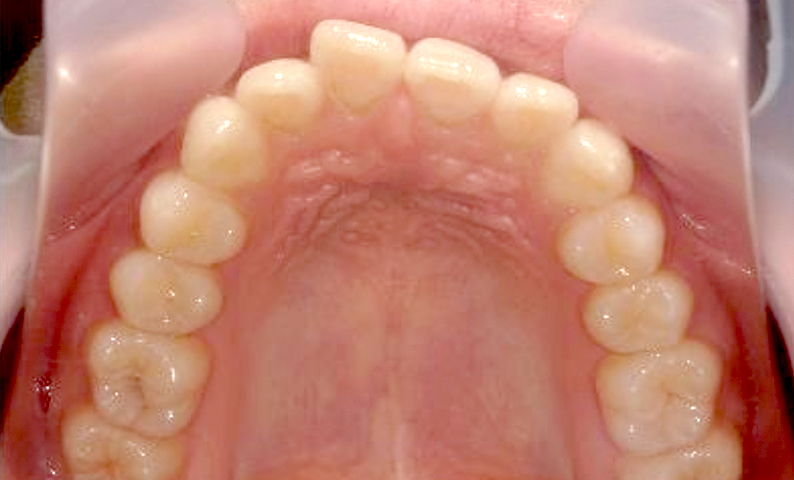

症例:上下顎の部分矯正

症例_002 前歯「捻転歯」症例

治療期間:10ヶ月金額:54万円+税30代女性少しのねじれ捻転歯前歯の突出感